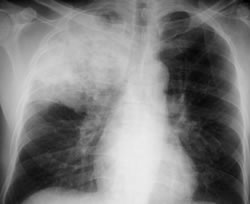

Tuberculosis Pulmonar: Causada por el Mycobacterium Tuberculosis, un gérmen agresivo que destruye el pulmón de manera lenta en la mayoría de las veces. El tratamiento disponible en nuestro país es excelente y eficaz, pero es el único por lo que el apego terapéutico es primordial. Los sintomas son: tos con expectoracion verdosa con o sin huellas de sangre, pérdida de peso, fiebres y sudoraciones vespertinas/nocturnas.